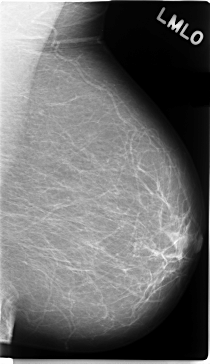

C_0121_1.LEFT_MLO

LEFT_MLO LINES 4720 PIXELS_PER_LINE 2720 BITS_PER_PIXEL 12 RESOLUTION 50 NON_OVERLAY